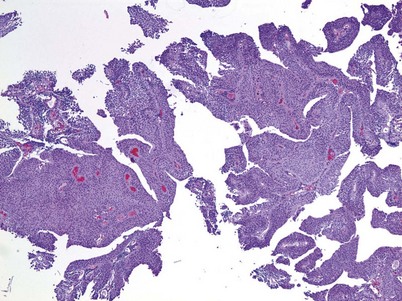

Cystitis cystica and/or glandularis is a common finding in normal bladders, usually associated with inflammation or chronic obstruction (Semins and Schoenberg, 2007). These benign tumors represent cystic nests that are lined by columnar or cuboidal cells and are generally associated with proliferation of Von Brunn nests (Figs. 80-3 and 80-4). Cystitis glandularis can be associated with pelvic lipomatosis and may occupy the majority of the bladder (Buckley et al, 2007). Cystitis glandularis may develop into or coexist with intestinal metaplasia, which are benign tumors characterized by goblet cells that are histologically similar to colonic epithelium. There have been a few case reports of cystitis cystica or glandularis transforming into adenocarcinoma, and therefore regular endoscopic evaluation of patients with these entities is recommended (Smith et al, 2008). The most common presenting feature of cystitis cystica or glandularis is irritative voiding symptoms and hematuria. Treatment is transurethral resection and relief of the obstruction or inflammatory condition.